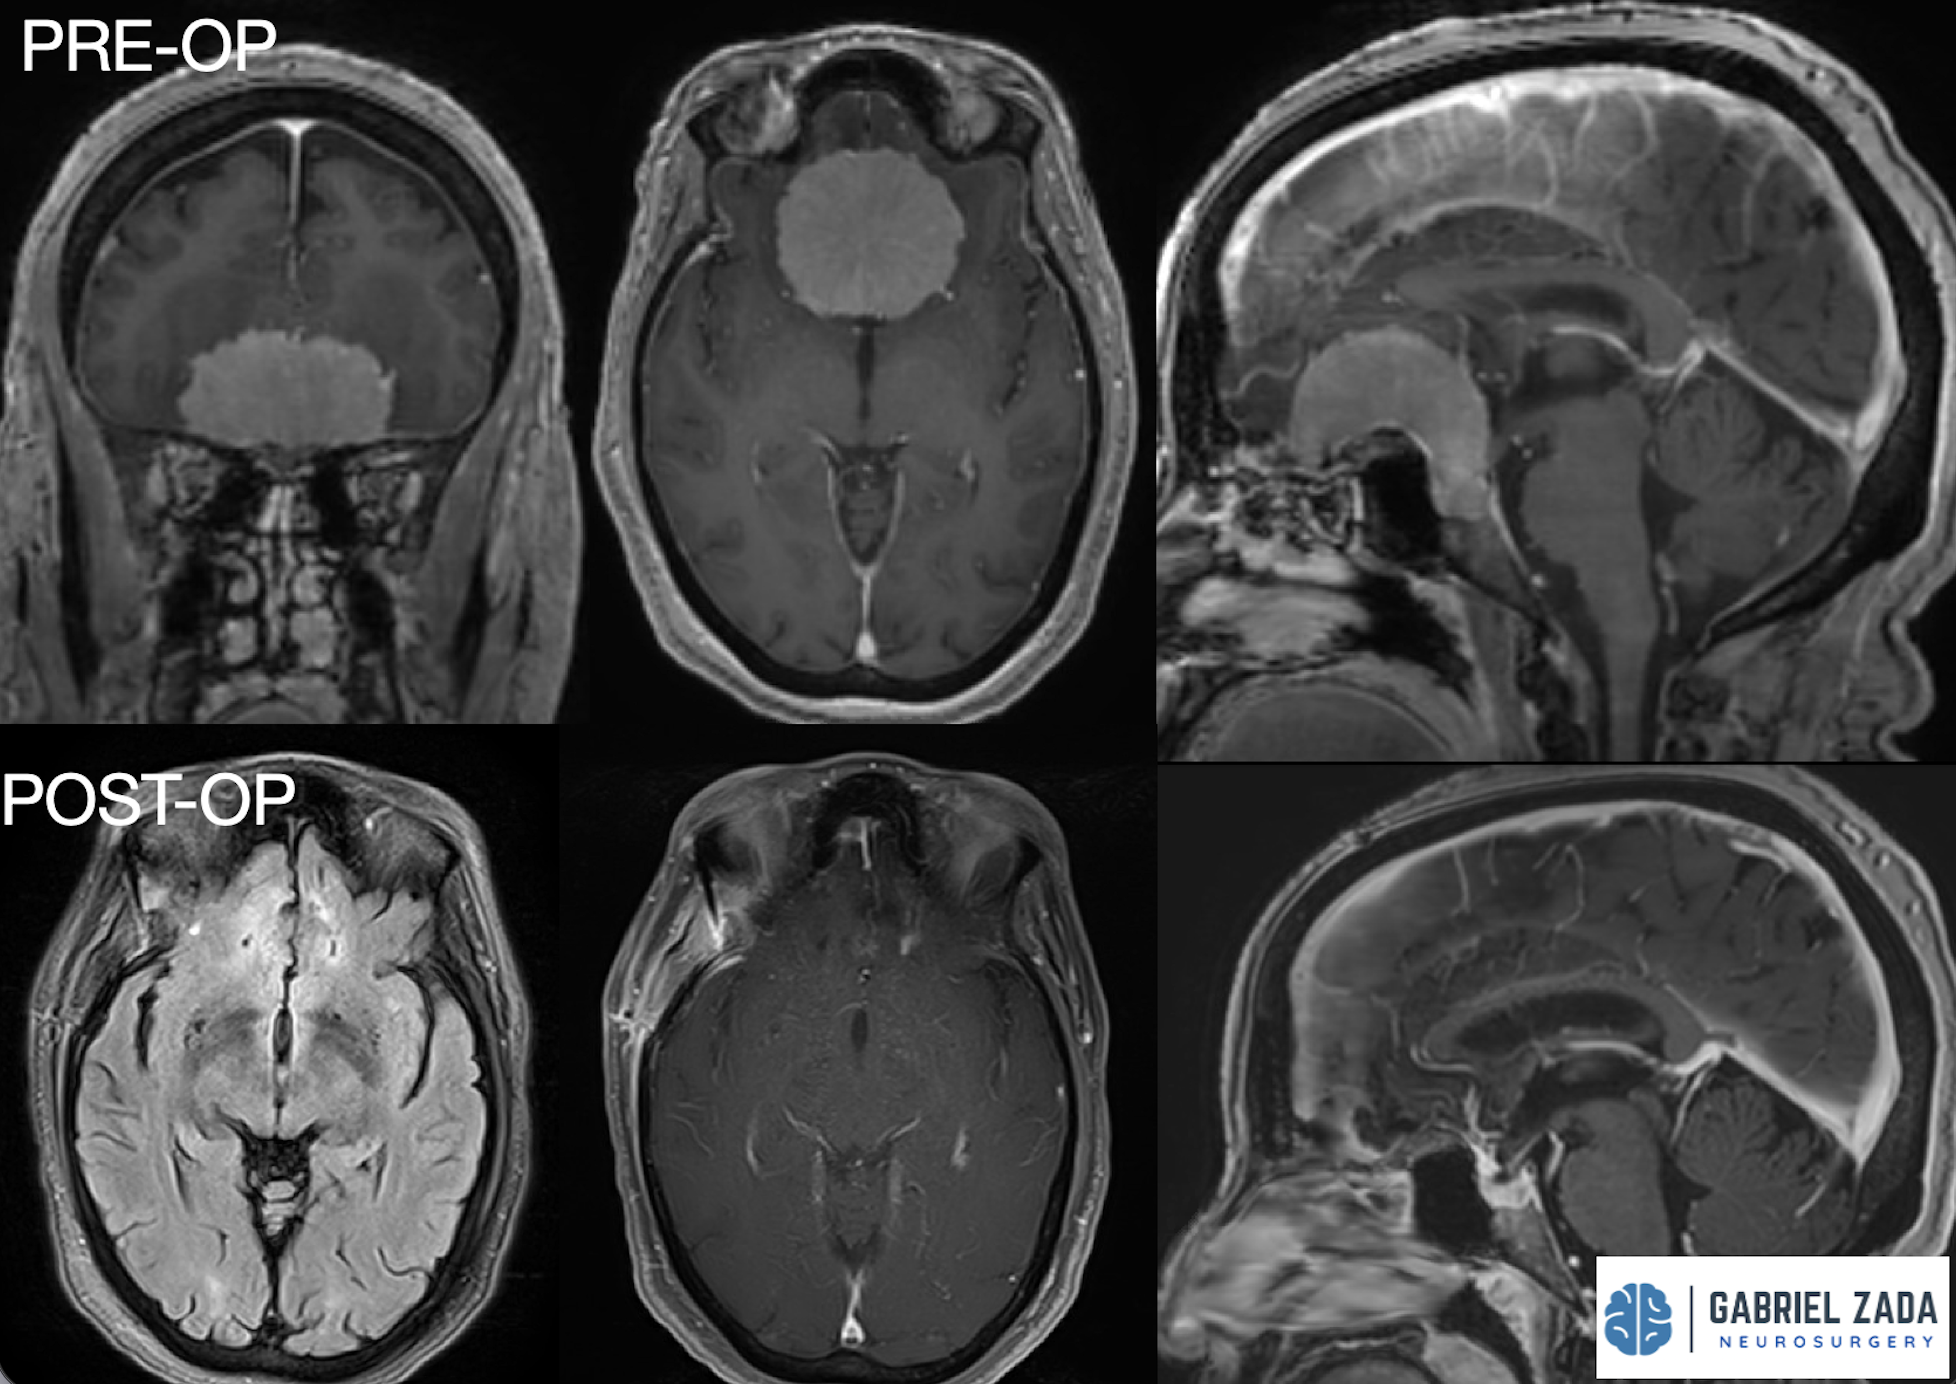

With extensive experience in advanced neurosurgical techniques, Dr. Zada provides personalized care for patients with meningiomas located in the brain and skull base. His approach emphasizes maximizing tumor removal while preserving neurological function, using modern imaging, microsurgical techniques, and minimally invasive approaches whenever possible.

Dr. Zada utilizes state-of-the-art neurosurgical techniques to safely remove meningiomas while protecting surrounding brain structures.

High-powered surgical microscopes allow precise tumor removal while minimizing damage to healthy tissue.

• Follow-up MRI imaging to monitor results

* Representative cases shown for educational purposes. All images de-identified. Individual results vary.